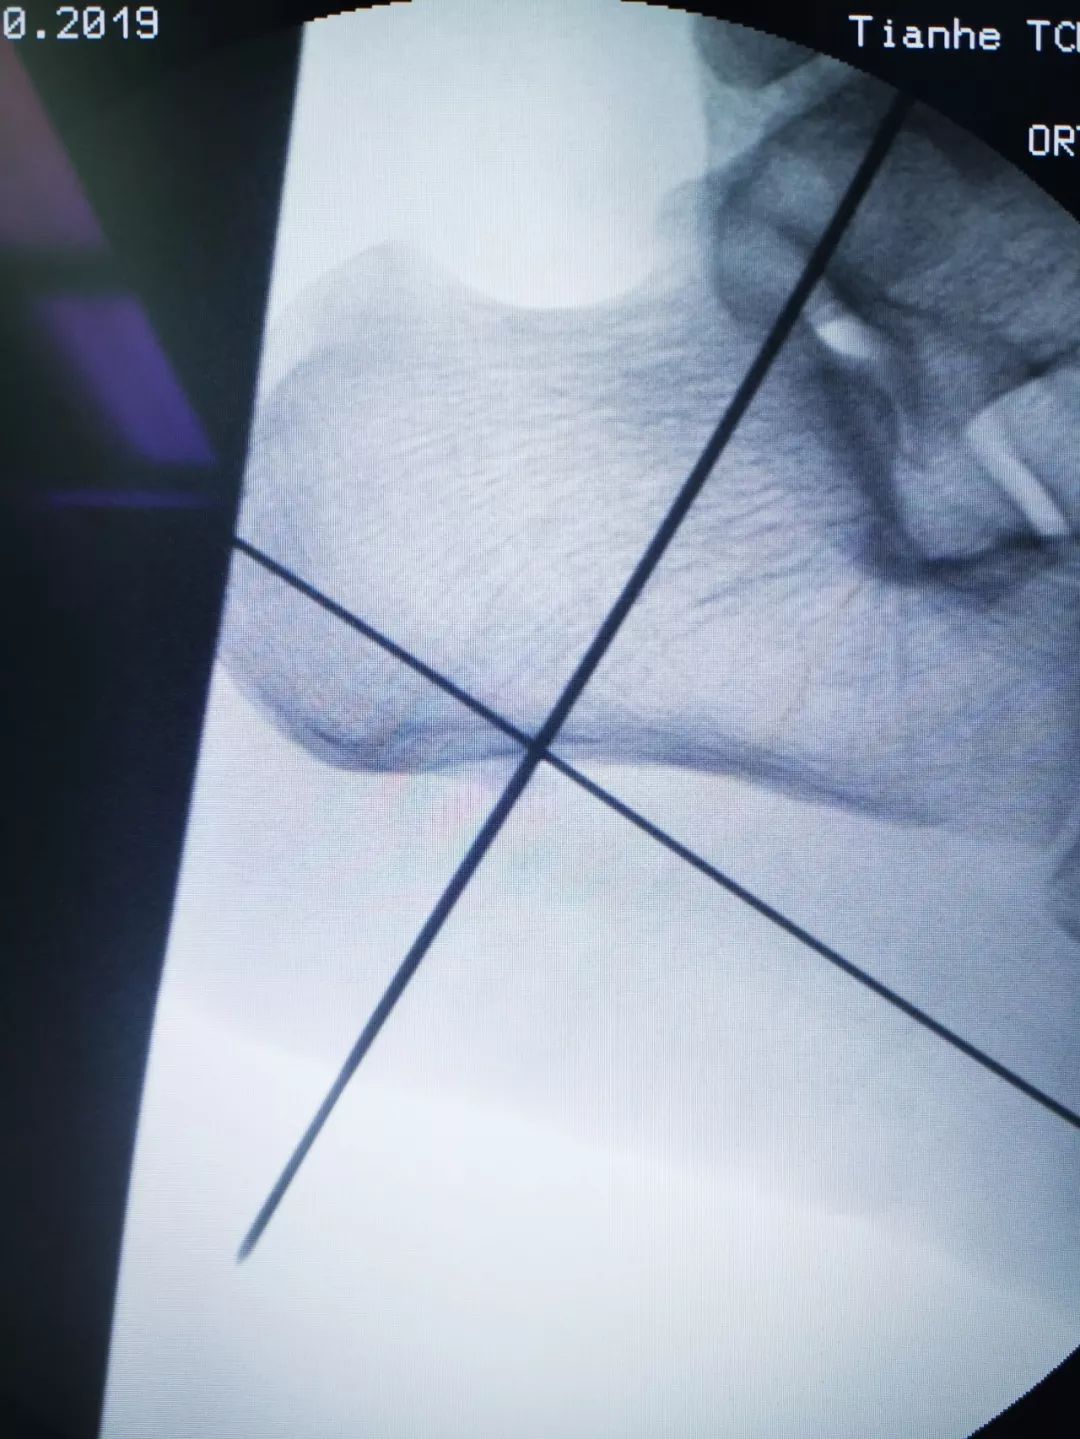

骨伤二科主任医师方磊经过与治疗团队认真讨论后,为患者制定了全新的微创手术方案,行关节镜下跟骨骨刺摘除术,手术取足跟部内侧两个0.5cm长小切口,在关节镜监视下切除增生骨赘,清理修整骨刺周围炎性组织,同时行跖筋膜松解,成功完成手术,目前患者术后恢复良好。